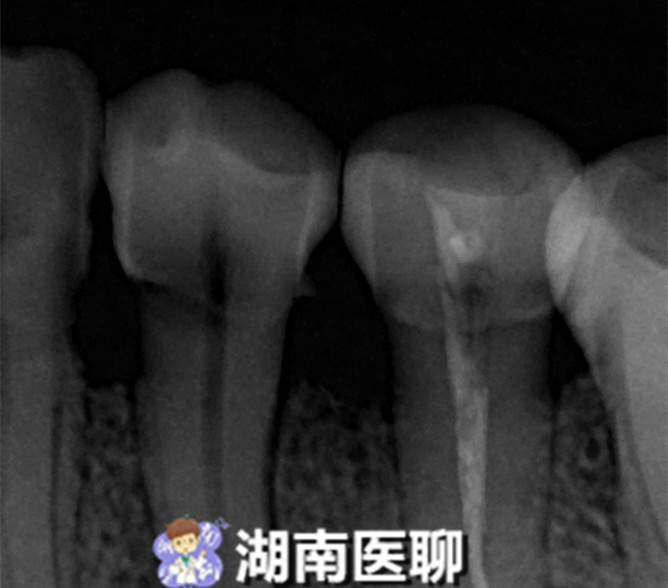

通过进一步详细询问病史、口腔检查及拍摄小牙片后,医生诊断为牙面上深达髓腔的深楔状缺损引发牙齿慢性根尖周炎,引起牙龈冒出脓包。

医生认为要想消除脓包,就要对牙进行根管治疗,消除炎症,于是患者接受了根管治疗,根管清理成形 ,补上了牙面上的深楔状缺损。